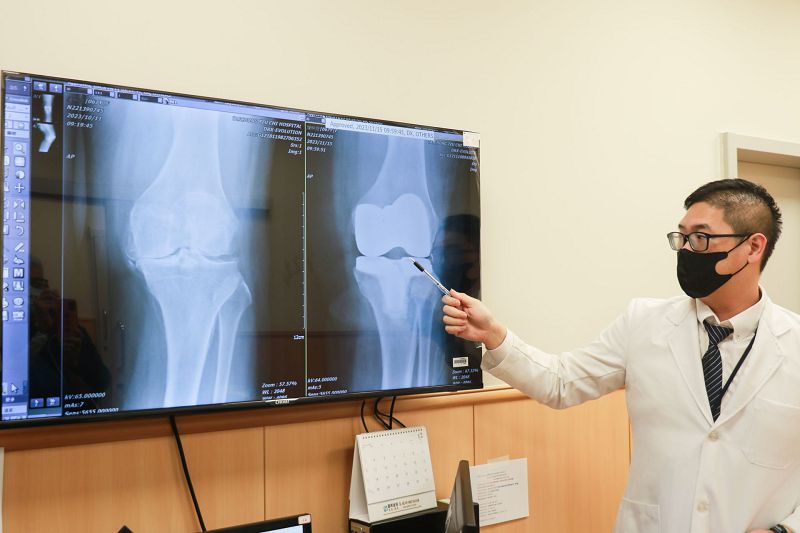

67歲陳女士膝關節疼痛多年,已經影響日常生活。台中慈濟醫院微創脊椎關節中心謝尚霖醫師診斷後,採用「ROSA Knee機器人手臂全人工膝關節置換手術」解除疼痛,術後膝關節疼痛與活動度顯著改善。

謝醫師指出,陳女士接受手術後,當日下午即下床使用拐杖助行器行走,出院一周回門診追蹤時,就能放開拐杖行走。膝關節疼痛與活動度顯著改善,口服止痛藥也減少很多,大幅提升生活品質。他解釋,ROSA Knee機器人手臂全人工膝關節置換手術,結合多項尖端科技,包括電腦智能運算、2D轉換3D立體解剖影像、即時定位追蹤導航、多動向機器人手臂等優勢,達到精準置換、減少軟組織傷害及術後疼痛與功能恢復,讓病人可以早期接受復健。